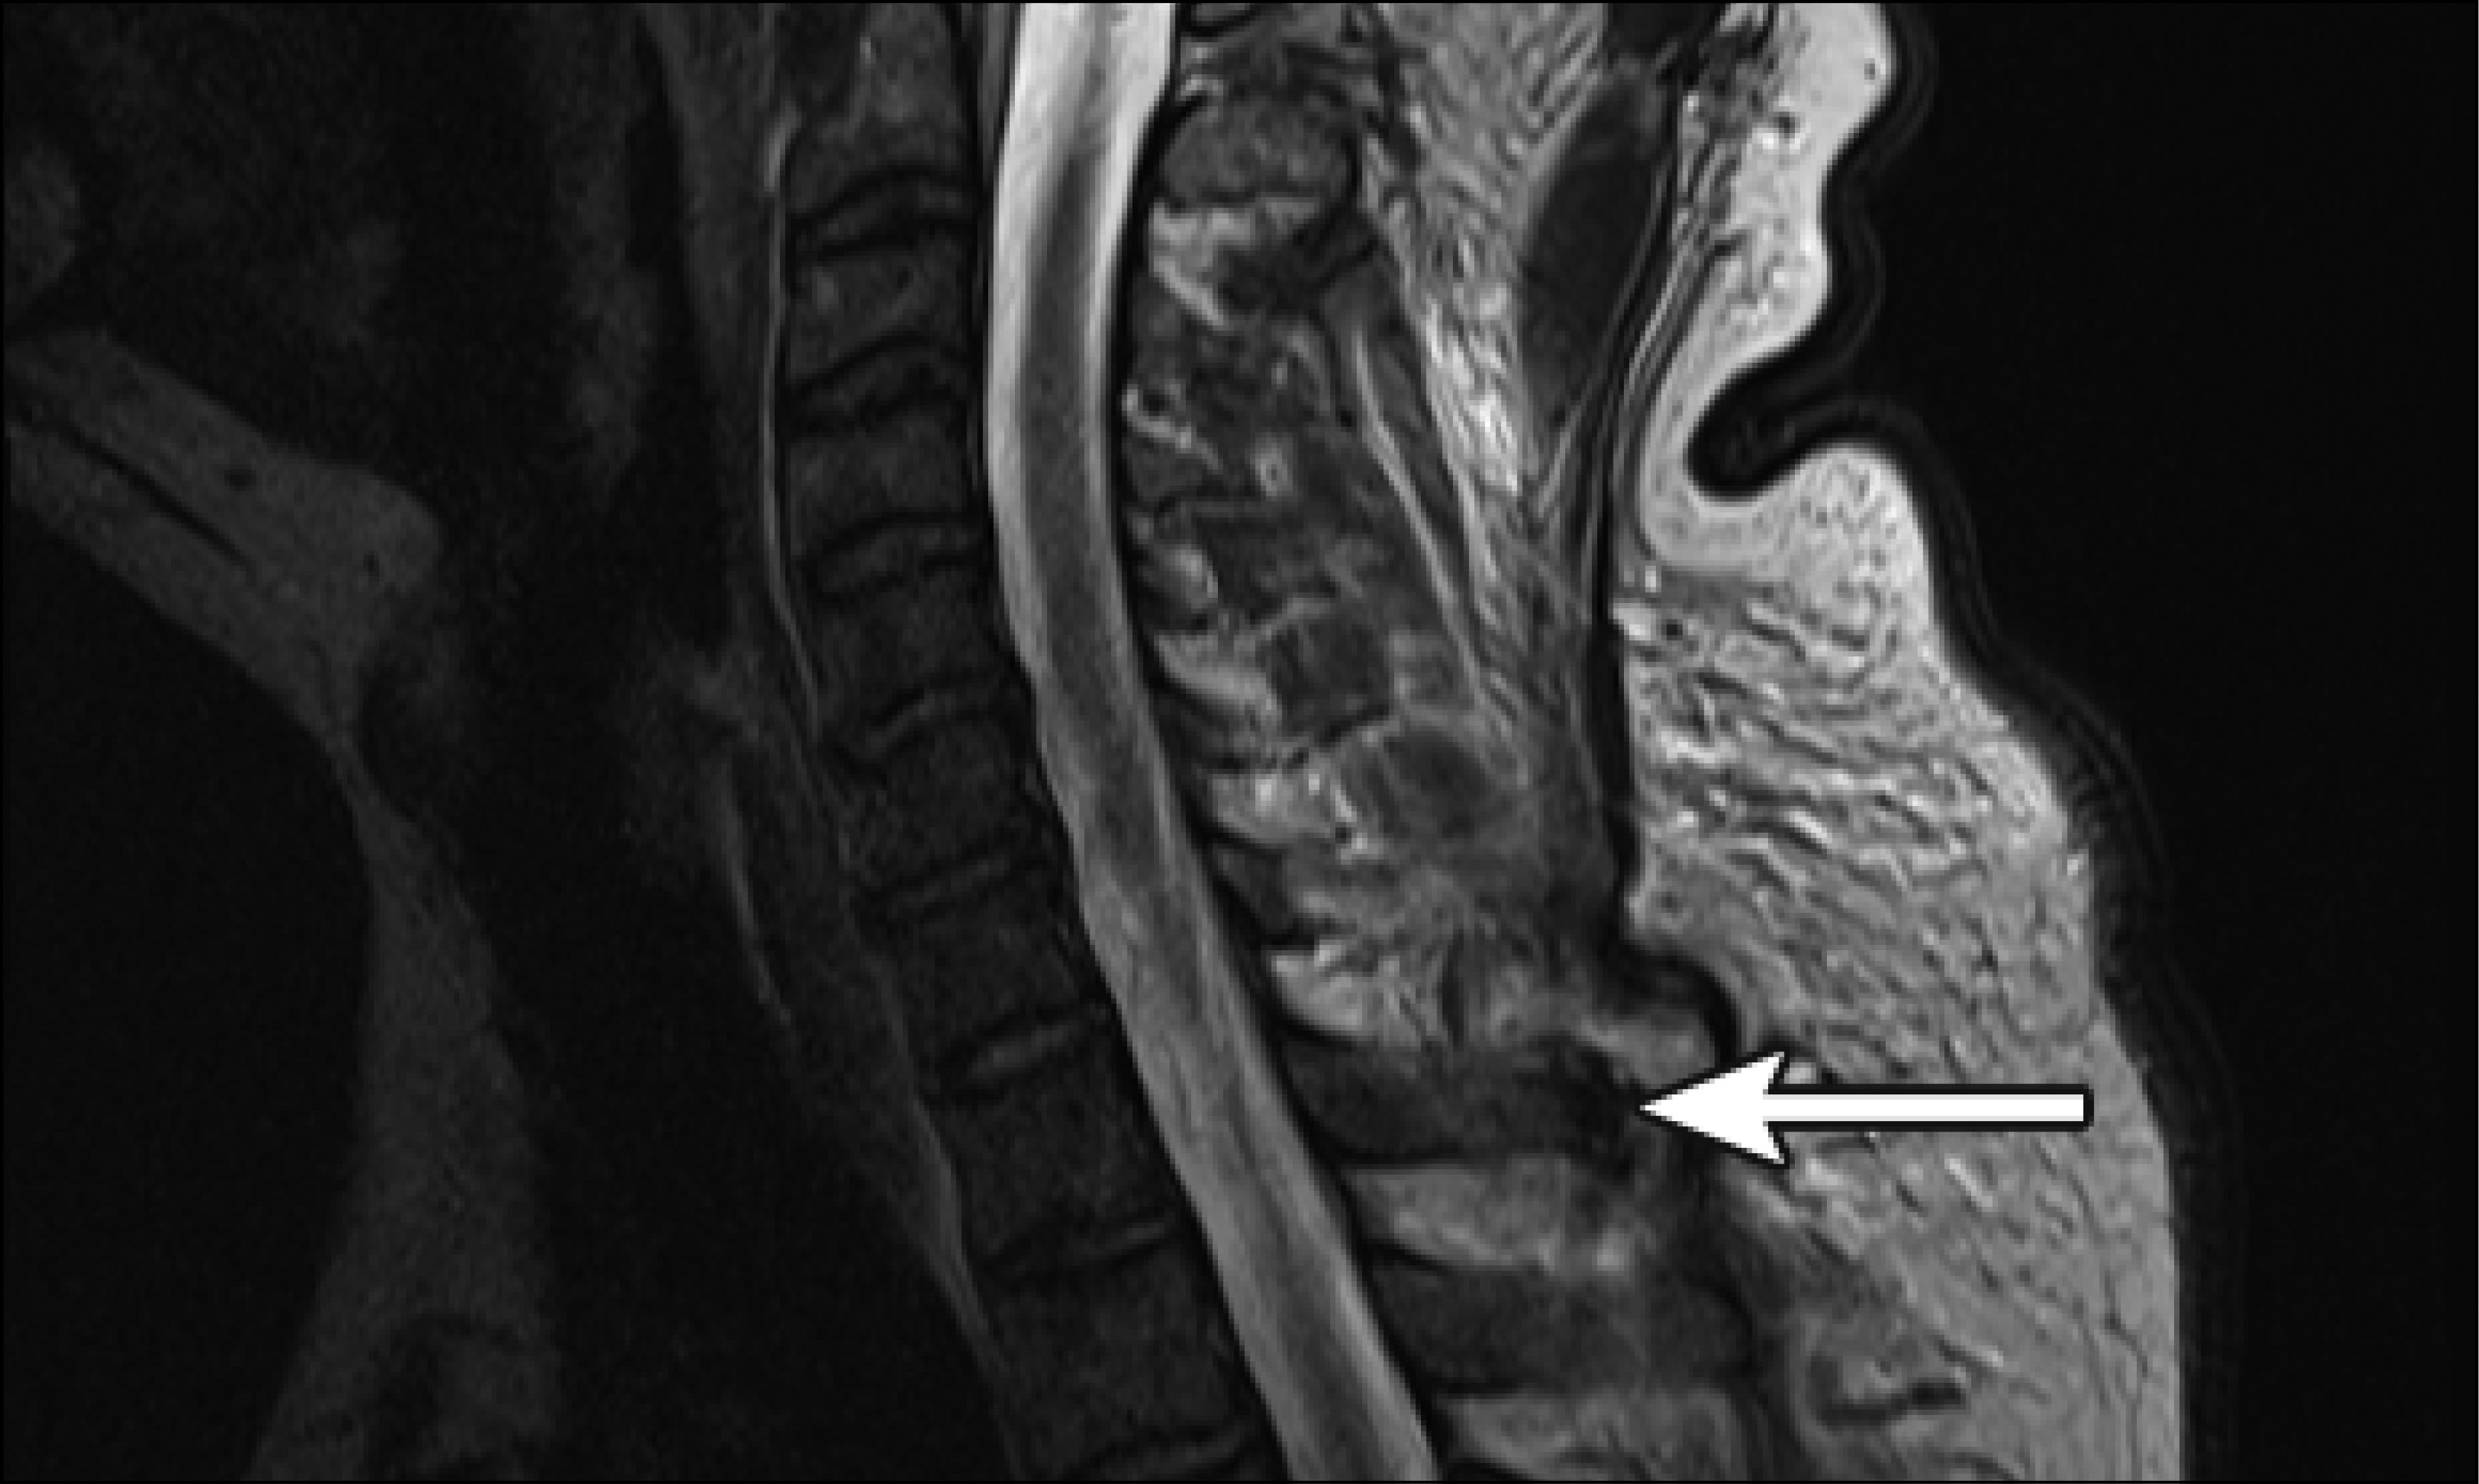

(PDF) Chronic tophaceous gout causing lumbar spinal stenosis Gouty Arthritis In Spine It is characterized by the saturation of. Symptoms of spinal gout can vary. How gout can affect the spine. Suspicion for spinal gout should remain high in the setting of intractable low back pain, especially in individuals with elevated risk. It’s caused by the buildup of a substance called uric acid in your joints. Gout is an inflammatory arthritis that. Gouty Arthritis In Spine.

Mri Lumbar Spine Arthritis Gouty Arthritis In Spine Gout is an inflammatory arthritis that most commonly affects the appendicular skeleton. How gout can affect the spine. It can cause back or neck pain and may be due to elevated. It is characterized by the saturation of. Symptoms of spinal gout can vary. Gout is a type of inflammatory arthritis that affects more than 8 million people in the. Gouty Arthritis In Spine.

Spinal gout mimicking osteomyelitis The Medical Journal of Australia Gouty Arthritis In Spine How gout can affect the spine. Gout is an inflammatory arthritis that most commonly affects the appendicular skeleton. It’s caused by the buildup of a substance called uric acid in your joints. Gout is a type of inflammatory arthritis that affects more than 8 million people in the united states. It can cause back or neck pain and may be. Gouty Arthritis In Spine.

Cervical spinal gout The Lancet Rheumatology Gouty Arthritis In Spine Multiple case reports and series describe the deposition of monosodium urate in the spine as a rare manifestation of gout, but. Suspicion for spinal gout should remain high in the setting of intractable low back pain, especially in individuals with elevated risk. It’s caused by the buildup of a substance called uric acid in your joints. Gout is an inflammatory. Gouty Arthritis In Spine.